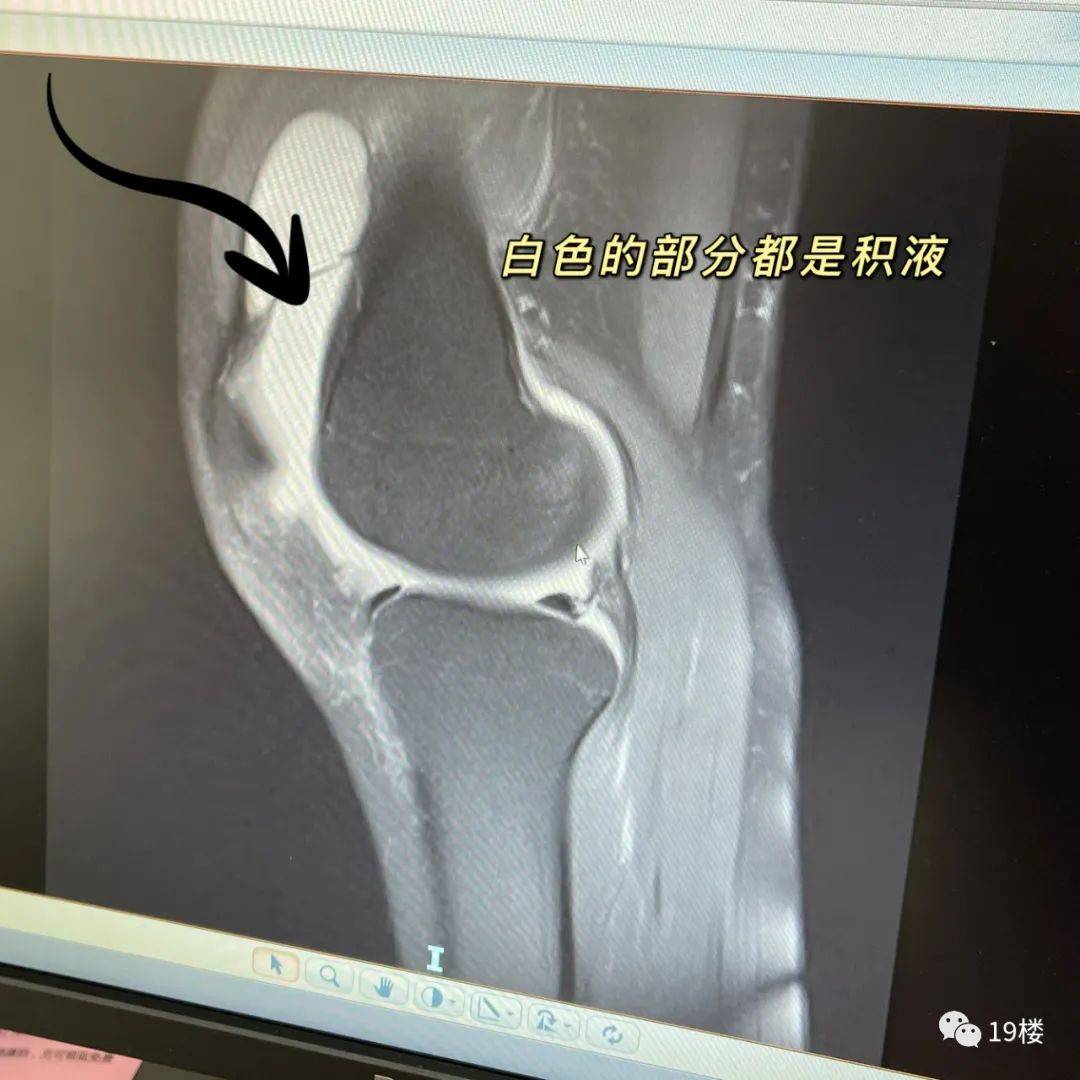

就诊时馒头大的膝盖里都是积液

之所以印象深刻 , 是因为这位患者确实“美丽冻人”:“这个女生年龄不大 , 才23岁 , 10月11号来医院就诊的 。我有印象那天已经开始下雨降温了 , 但是当时她还穿着短裤 。 一进门我就看到她一侧膝盖已经整个肿起来 , 像个大馒头 , 情况已经比较严重了 。 ”

孙主任说 ,在排除了外伤的前提下 , 他判断女生是由于滑膜炎而引发的积液 , “因为来医院之前她的膝盖已经痛了十来天 , 而且这期间还在上班 , 膝盖没有得到休息 , 也没有做好保暖 。 ”

做过检查后 , 果然膝盖里的空隙处都是液体 。 “我当时给她把积液抽出来 , 针筒扎进去 , 都不用抽 , 关节里的压力就压着积液直接流了出来 。 我叮嘱她回去戴一段时间的半月板护膝 ,然后多休息 , 减少走路 , 避免爬山、爬楼梯 , 注意保暖 , 之后也要适当进行运动 。 ”